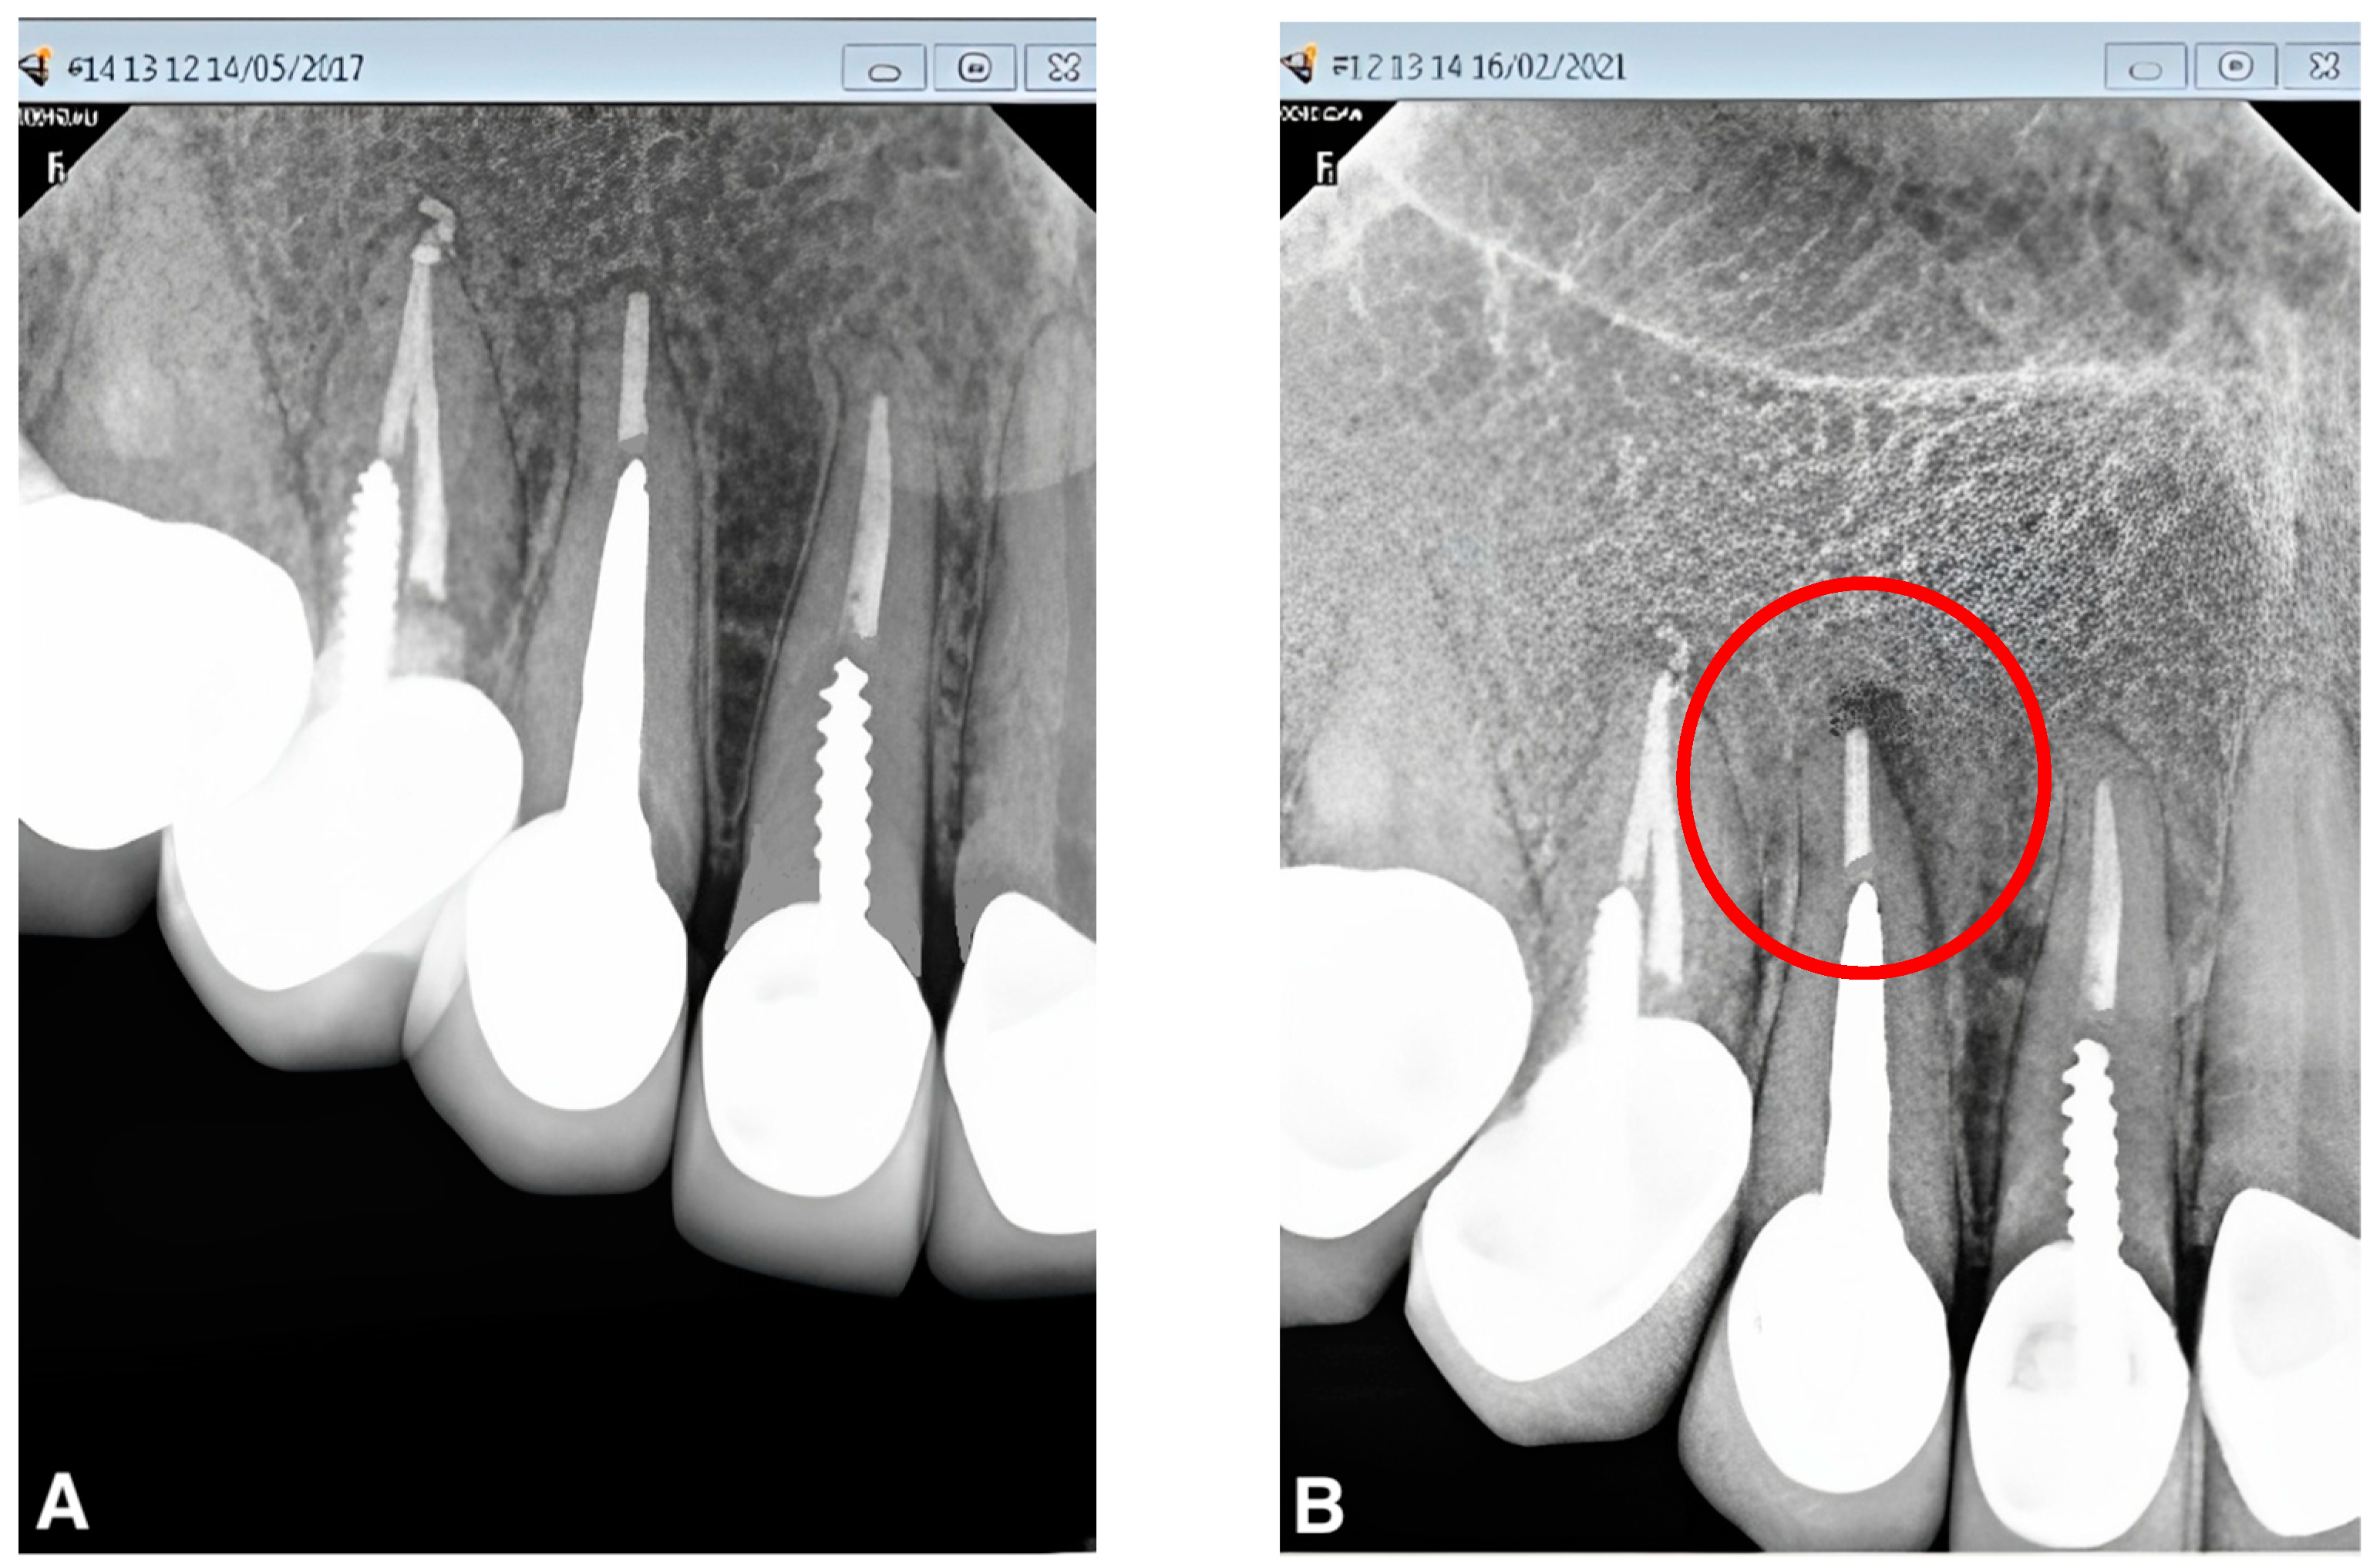

From www.jendodon.com

Retrieval of Extensive Guttapercha Extruded into the Maxillary Sinus Gutta Percha Side Effects Gutta percha is commonly used as a root canal filling material. Learn about the reasons, symptoms, procedure, pain, cost, and. A root canal is a treatment of the pulp of the tooth that is inflamed, infected, or dead. Find out the signs, causes,. Learn about the benefits and drawbacks of root canal treatment, a procedure to preserve a decayed tooth.. Gutta Percha Side Effects.